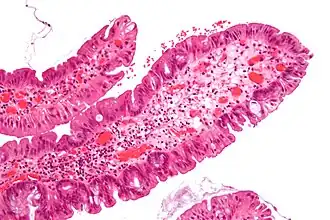

| Adénome dentelé sessile | Semblable à hyperplasique avec hyperserration, bases des cryptes dilatées/ramifiées, des cellules de mucine apparents à la base des cryptes | Oui | ![]() |

||